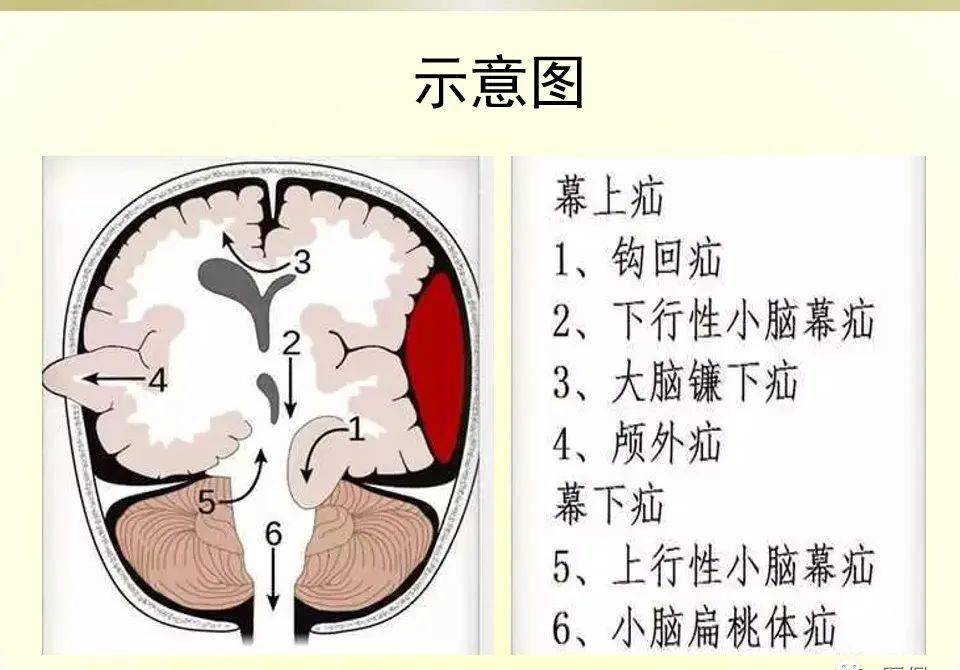

颅内疝包括:大脑镰下疝,中心疝,海马钩回疝,小脑扁桃体下疝.

血管及脑神经等重要结构受压和移位,被挤入硬脑膜的裂隙或枕骨大孔